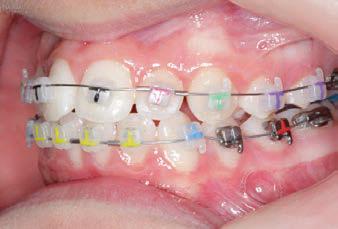

CLASS II DIV.1 - Marra

PROGRESS 1 - 26/9/18 - Class I platform accomplished in 5.75 months with Motion 3D COLOR Appliance

PROGRESS 2 - 26/9/18 - Placement of the SLX 3D Clear Brackets

with M-ONE .015 Cu Nitanium 27°

PROGRESS 3 - 30/10/18 - With M-TWO .020 x .020 Cu Nitanium 35° archwire

PROGRESS 4 - 27/11/18 - 3 links power chain: 5, 4, bypass 3 to crimp hooks

PROGRESS 5 - 13/3/19 - With M-TWO .020 x .020 Cu Nitanium 35° archwire

PROGRESS 6 - 1/8/19 - With M-THREE.019 x .025 Beta Titanium wire